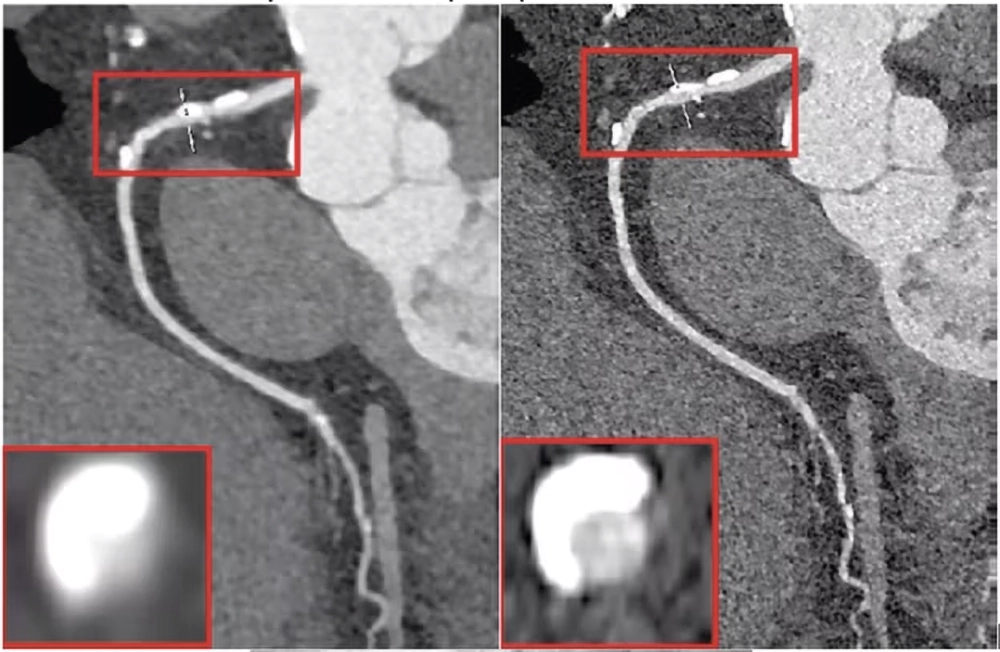

Representative cases demonstrated that ultrahigh resolution imaging reduced blooming artifacts from calcified plaques, which is a notable limitation in conventional and standard resolution CT imaging.

The study highlights that both standard resolution and ultrahigh resolution PCCT protocols achieve high diagnostic performance in detecting significant coronary stenosis, validated against invasive coronary angiography. However, the enhanced spatial resolution in ultrahigh resolution modes notably improves visualization, particularly in vessels heavily affected by calcification, reducing blooming artifacts and potentially minimizing false-positive assessments.